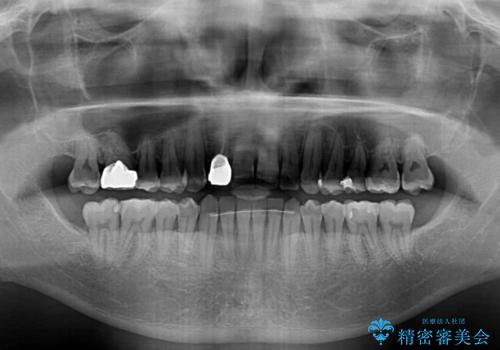

治療途中の前歯を治したい インビザライン矯正とオールセラミッククラウン

- 治療途中の前歯と上下前歯のデコボコ気にして来院された患者様です。

前歯のデコボコはインビザラインにより歯列を整え、その後に、前歯などをオーダーメイドタイプのオールセラミッククラウンにて補綴治療することとしました。

長時間のマウスピース装着に協力いただき、短期間で歯列をしっかりと改善することができました。

ホームホワイトニングを併用していただいたので、とても明るい口元に仕上がり、患者様には大変満足していただきました。